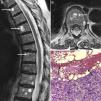

Resonancia magnética de columna dorsolumbar mostrando, en los cortes sagital (A) y axial (B) de la secuencia potenciada en T2, la presencia de múltiples lesiones vertebrales con niveles líquido-líquido típicos, con hiperseñal en el nivel superior e hiposeñal en el inferior. La biopsia ósea (C) reveló que dichas lesiones correspondían a metástasis de un adenocarcinoma pobremente diferenciado con células en anillo de sello (cabezas de flechas), rodeando un contenido hemorrágico (flechas) (hematoxilina-eosina 10×).

Una paciente de 76 años consultó por dolor lumbar y pérdida de peso de 6 meses de evolución. Había sido diagnosticada de esclerosis sistémica (ES), con enfermedad pulmonar intersticial asociada 5 años antes, y recibió como terapia de inducción ciclofosfamida durante 18 meses (6 ciclos mensuales y 4 trimestrales), seguido por azatioprina y glucocorticoides a dosis bajas como terapia de mantenimiento. En la exploración física, presentaba caquexia y dolor difuso a la presión de las apófisis espinosas. Las radiografías de columna mostraban un aplastamiento vertebral anterior de D8 y la resonancia magnética (RM) reveló múltiples lesiones vertebrales redondeadas con niveles líquido-líquido, que tenían hiperseñal en el nivel superior secuencia potenciada en T2 y señal intermedia en la secuencia T1, e hiposeñal en el nivel inferior en ambas secuencias (fig. 1A y B). La biopsia ósea demostró que dichas lesiones correspondían a metástasis de un adenocarcinoma pobremente diferenciado con células en anillo de sello, rodeando un contenido hemorrágico (fig. 1C). Desde el punto de vista inmunohistoquímico, las células tumorales expresaban citoqueratina 7 y proteína-15 del líquido de la enfermedad quística, indicando un probable origen mamario. Sin embargo, no se encontró el tumor primario en el estudio de extensión, que incluyó mastografía bilateral, tomografía computarizada cráneo-cervical y toraco-abdomino-pélvica, gammagrafía ósea completa, endoscopia digestiva alta y colonoscopia. La paciente fue tratada con paclitaxel más carboplatino, analgesia de tercer escalón, zoledronato y radioterapia paliativa, permaneciendo estable durante un período de seguimiento de 6 meses.